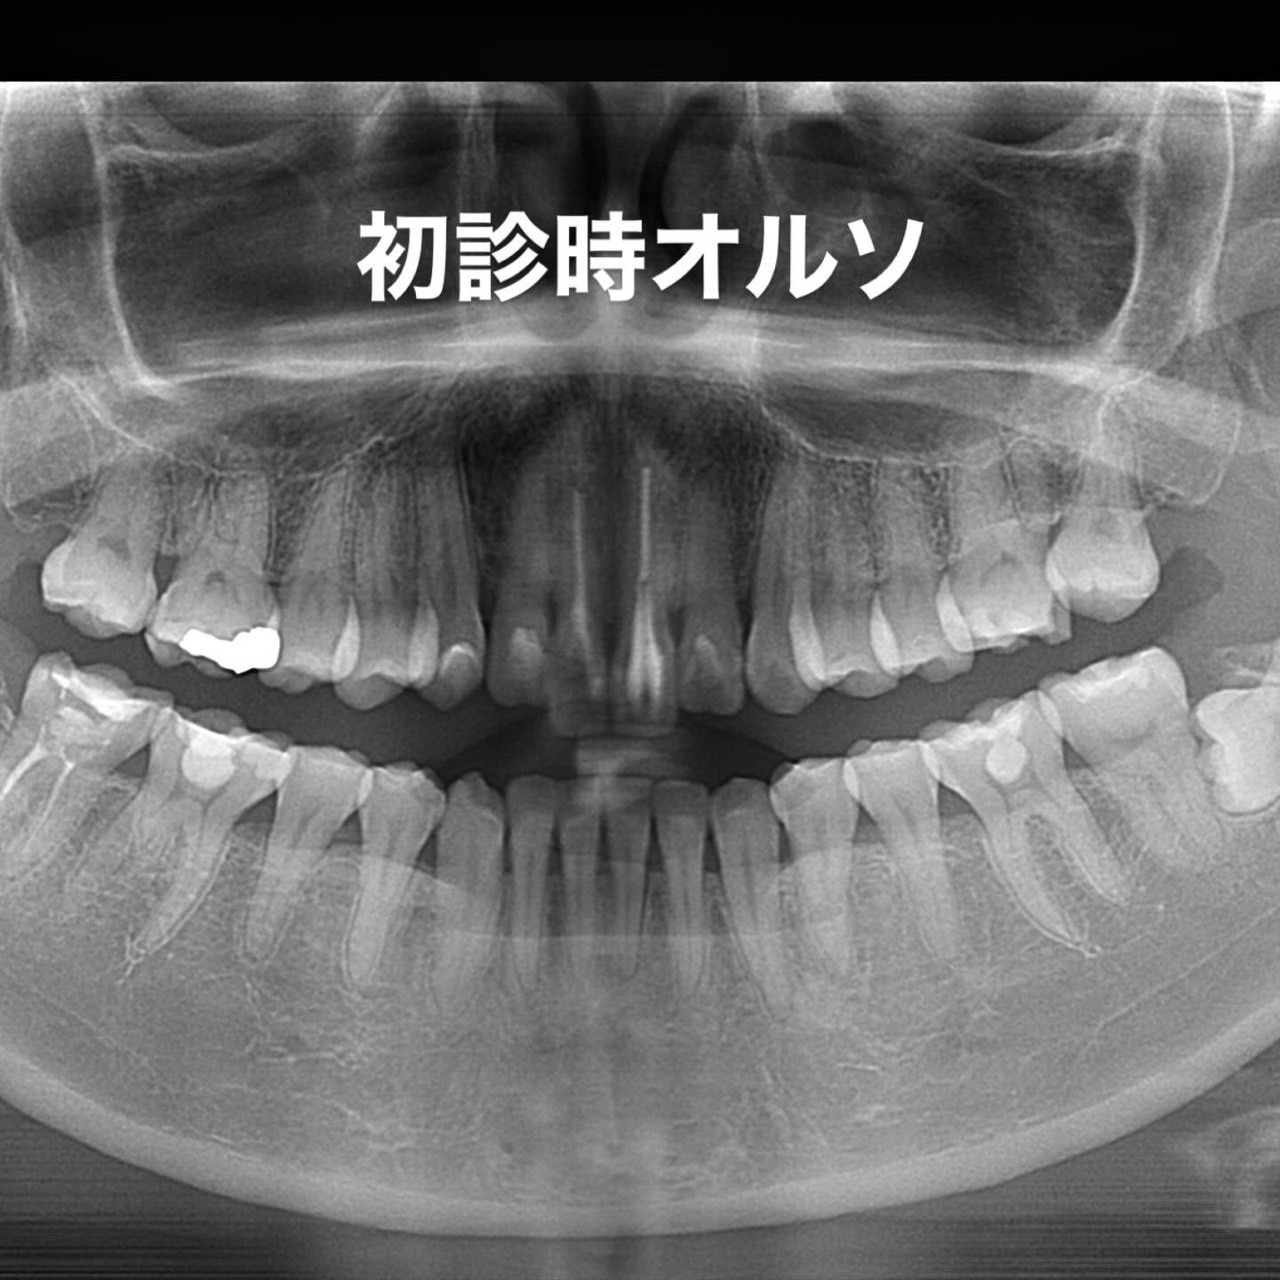

Case023

噛み合わせから審美的なところまで、トータルで治療させて頂いた患者様です。

ここまでやるとなると、できないクリニックもありますし、できるところでも年単位でかかってしまうクリニックが大半だと思いますが、今回は4月末にカウンセリングでご来院いただき、5月に治療をスタートして9月末には診療が終わっています。

治療回数や、治療期間がかかってしまうと、患者様も通院が辛くなったり疲れてしまったりしてしまうと思います。どんどん綺麗になっていく、食事がしやすくなっていくという実感がある方が患者様に楽しく治療に臨んでいただけると思うので、私は診療のスピード感を大切にしています。

トータルでやらせていただいたので、噛み合わせなどの機能面から外見などの審美性もかなり良くなり、患者様にも満足して頂けてよかったです。

治療期間 約4ヶ月